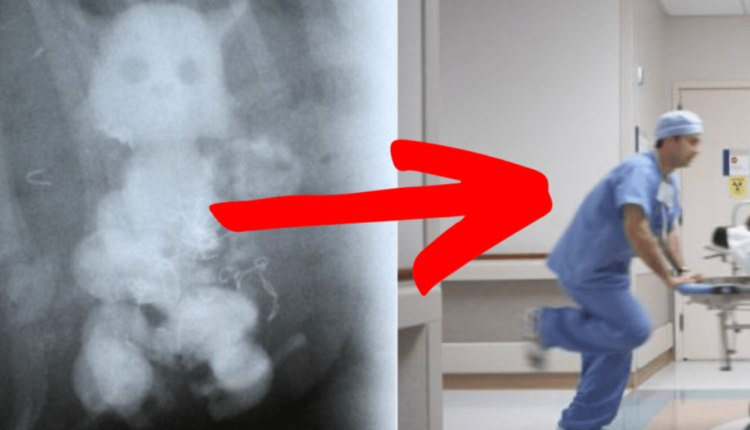

Um idoso, cuja identidade permaneceu oculta, protagonizou um episódio digno de roteiro de filme. Sem aviso prévio, ele se viu nas garras da urgência médica devido a um incidente tão incomum quanto alarmante: uma boneca de plástico alojada em uma parte do seu corpo que desafiava qualquer lógica.

A saga do idoso e sua inesperada companheira plástica logo se desenrolou, revelando detalhes ainda mais surpreendentes. Após uma corrida contra o tempo, ele foi levado a uma unidade médica onde, para espanto geral, a presença da boneca foi confirmada por profissionais da saúde.

O drama ganhou contornos épicos quando se cogitou a necessidade de uma intervenção cirúrgica para remover o intruso inanimado. No entanto, a reviravolta nessa trama médica deixou a todos boquiabertos: o idoso conseguiu expelir a boneca sem a necessidade de uma cirurgia, desafiando as expectativas mais pessimistas.